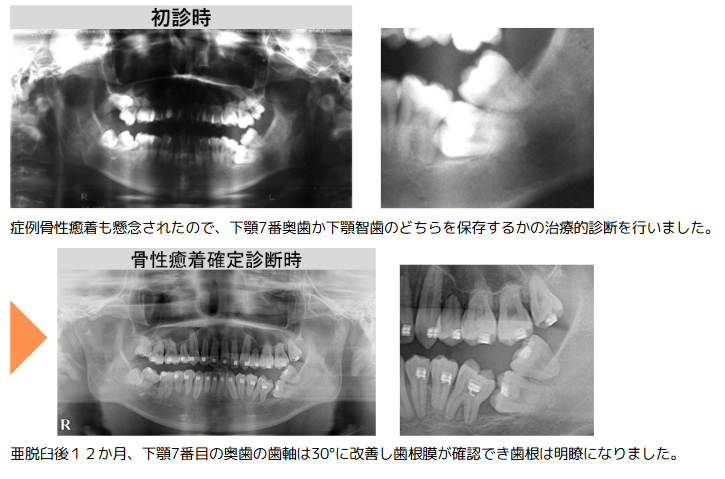

水平の下顎左側奥歯の7番に智歯が覆い被さる重積状埋伏の状態を呈していました。骨性癒着の可能性もあったため、原因が不明な症状に対し原因を仮定して治療を行い、その反応から原因を特定する方法で治療を進行。治療の途中では骨性癒着が認められたため、亜脱臼による剥離術を実施。また、喫煙習慣があることから歯周病の治療も併用し、下顎左側奥歯の7番と智歯の両方を直立させました。直立後の経過観察において、下顎左側奥歯の7番の近心に歯槽骨の増骨反応が認められたため、同部位の保存を決定しました。もし保存が困難だった場合は智歯を活用する「二の矢」を視野に入れ、診断段階から複数の治療シナリオを想定しています。

治療内容